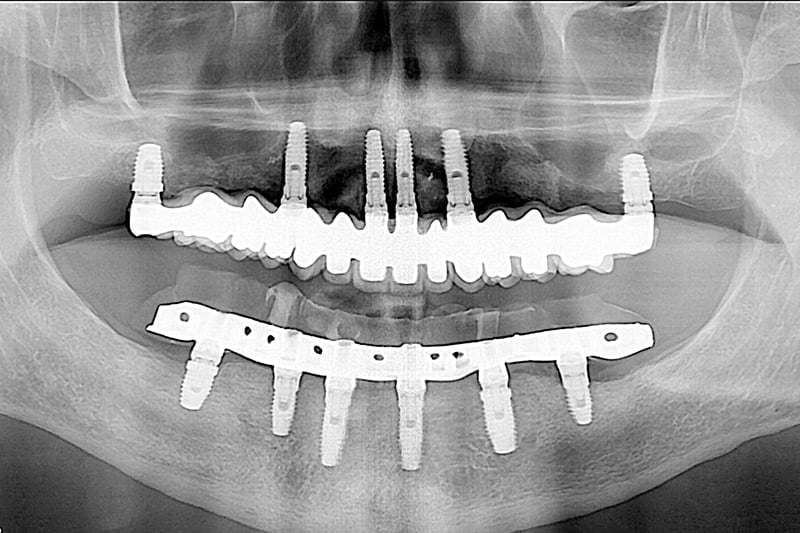

La solución que planteamos para resolver su caso fue una rehabilitación total, en una sola sesión y bajo sedación. Retirando todos los dientes afectados por la periodontitis y los implantes antiguos en mal estado, y colocando en una sola sesión implantes nuevos y saneando todos los tejidos, en el mismo día le colocamos la nueva prótesis fija provisional. Cuando los tejidos curaron y maduraron pudimos terminar con las prótesis definitivas de alta estética.